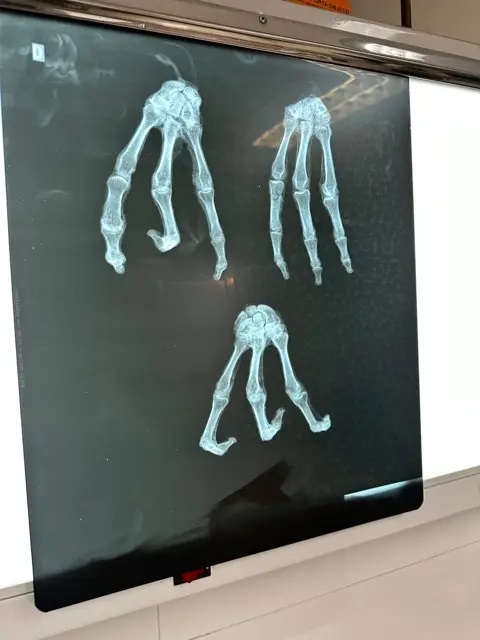

Các nhà làm phim cho biết 'xác ướp ngoài hành tinh' ba ngón kỳ lạ là có thật và chứa DNA độc nhất

Các nhà làm phim Michael Mazzola và Serena DC cho biết họ đang ghi lại bằng chứng về “xác ướp người ngoài hành tinh” giống như những xác ướp đã gây chú ý ở Peru năm ngoái.

Các nhà làm phim cho biết tia X và các xét nghiệm khác chứng minh mẫu vật của họ là hàng thật.

Serena và Mazzola cho biết một phân tích cho thấy số liệu của họ có 30% DNA “không xác định” .